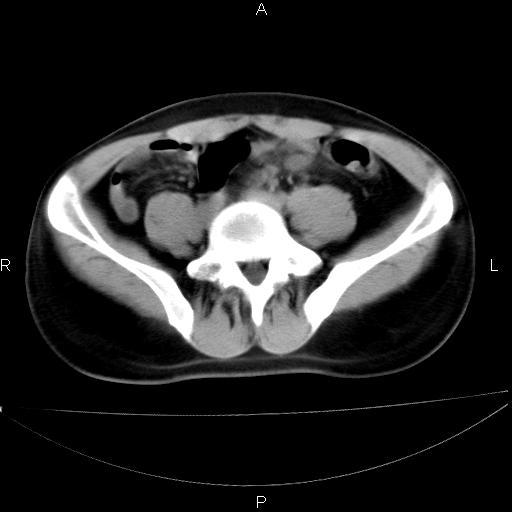

男 25岁 自述 尿频尿急,排尿困难20多天.无腰痛, b超说左肾盂轻度积水,左输尿管上端扩张.未见结石影. ct我看双侧肾盂轻度积水,双输尿管上端都扩张,大家看看能看见结石吗?

考虑肾外肾盂 前列腺轻度肿大 密度欠均 考虑炎性改变

箭头所指不是输尿管,壶腹型肾盂。

肾外肾盂,必要时+c